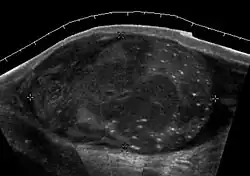

Fig. 23. Tubular ectasia of the testis. Honey-comb shaped cystic lesion at mediastinum testis.

Fig. 24. Tubular ectasia of the testis. Lesion in the testis mimicking testicular tumor, but the microcystic appearance of this lesion is suggestive of tubular ectasia.

The normal testis consists of several hundred lobules, with each lobule containing several seminiferous tubules. The seminiferous tubules of each lobule merge to form the straight tubes, which in turn converge to form the rete testis. The rete testis tubules, which lie within the mediastinum testis, are an anastomosing network of irregular channels with a broad lumen, which then empties into the efferent ductules to give rise to the head of the epididymis. Obstruction in the epididymis or efferent ductules may lead to cystic dilatation of the efferent ductules, which usually presents as an epididymal cyst on ultrasound. However, in the more proximal portion this could lead to the formation of an intratesticular cyst or dilatation of the tubules, so-called tubular ectasia. Factors contributing to the development of tubular ectasia include epididymitis, testicular biopsy, vasectomy or an aging process. Clinically this lesion is usually asymptomatic. The ultrasound appearance of a microcystic or multiple tubular-like lesions located at the mediastinal testis [Fig. 23] and associated with an epididymal cyst in a middle-aged or elderly patient should alert the sonographer to the possibility of tubular ectasia. The differential diagnosis of a multicystic lesion in testis should include a cystic tumor, especially a cystic teratoma. A cystic teratoma is usually a palpable lesion containing both solid and cystic components; and the cysts are normally larger than that of tubular ectasia, which appear microcystic [Fig. 24]. Furthermore, the location of tubular ectasia in the mediastinum testis is also helpful in making the differential diagnosis.